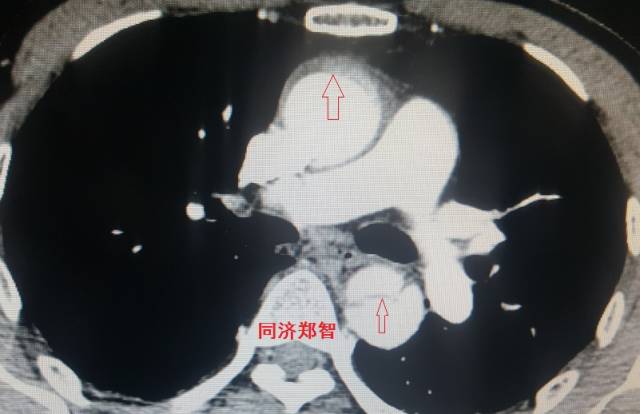

病例二

胸部平扫CT提示升主动脉增宽(红色星形标记),CTA证实A型主动脉夹层伴升主动脉夹层动脉瘤形成。